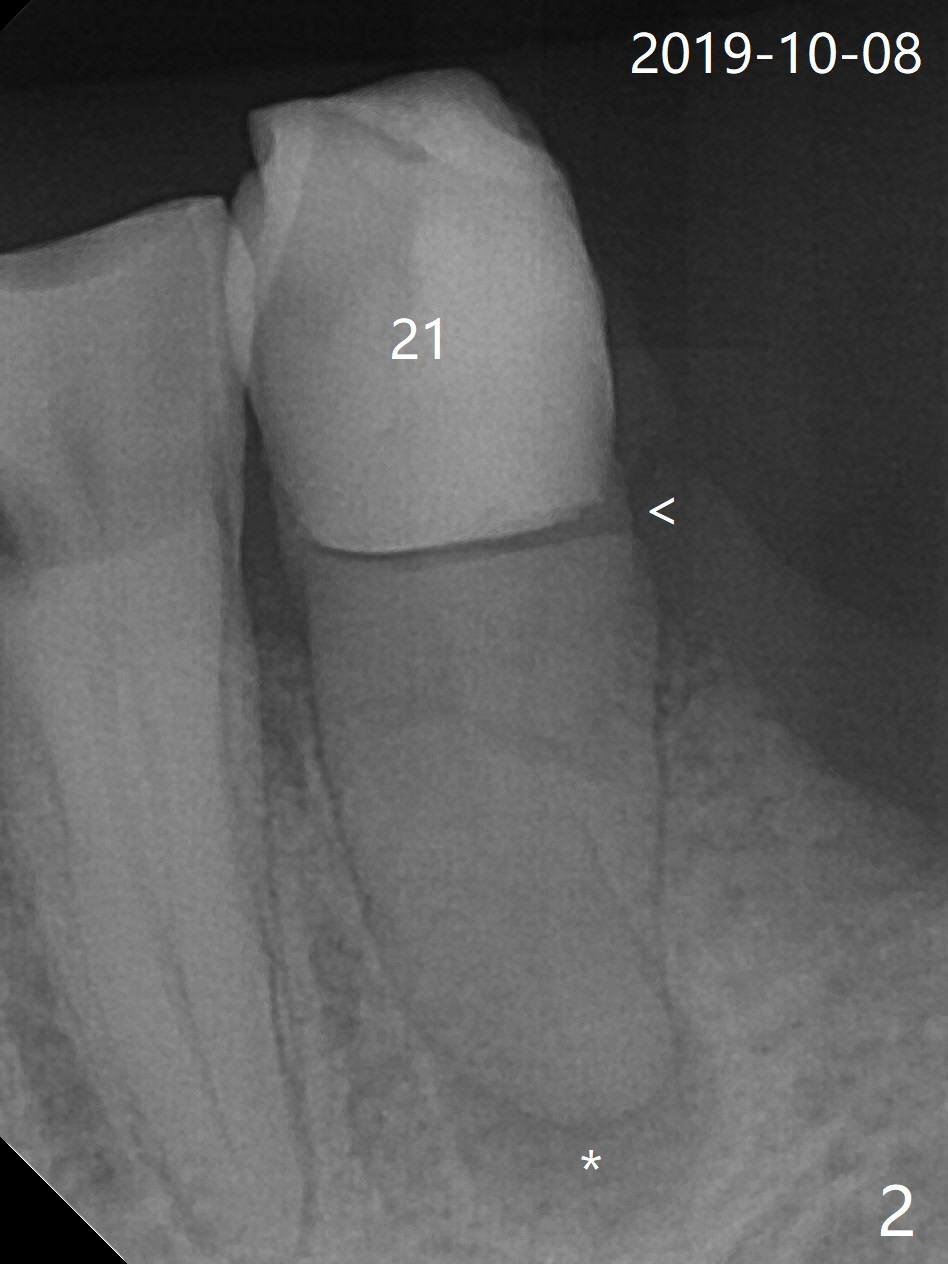

A 85-year-old woman has had poor dentition (Fig.1). She requests extraction of the tooth #21 with crown fracture (Fig.2 <) and PARL (*). Although the buccal plate is low, Vanilla/Osteogen mixture is used for socket preservation (Fig.3 *), while BioXclude is used to cover the socket opening. Three to four 5-0 PGA sutures appear to be able to close the socket. It is expected that the membrane with several growth factors facilitates wound healing. It seems that the bottom of the socket is not fully packed with the bone graft (Fig.3 ?). Bone condenser should have been utilized. The socket appears to heal (due to BioXclude?) with minor buccal plate collapse 1 week postop (Fig.4). Titanium membrane should have been used.